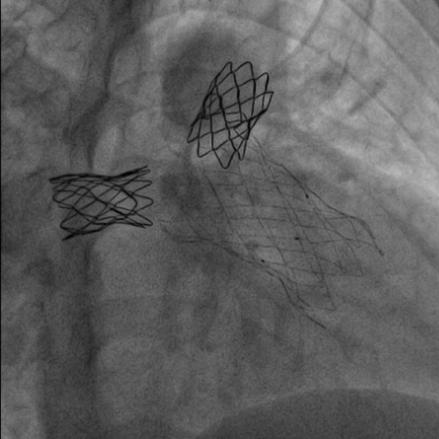

患者在全麻下,首先从左股静脉将造影导管分别送至右心室和肺动脉主干,行造影以明确右室流出道、肺动脉及肺动脉分支的基本情况。同时测量了右室流出道及肺动脉的尺寸。随后输送器通过右侧股静脉延加硬导丝将瓣膜输送到右室流出道,在X线的引导下,将瓣膜精确定位到植入部位并顺利进行瓣膜释放,无反流和瓣周漏,手术效果十分理想。

高主任总结道:本例病例就是在没出现严重肺动脉反流时,先解决了严重的左右肺动脉分支起始部狭窄,不仅促使狭窄远端肺血管的发育,避免了肺动脉分支的闭塞。随着年龄长大,肺动脉反流加剧,右心功能受损时,我们及时植入肺动脉带瓣支架,阻滞了右心功能向失代偿期的发展。

随着介入技术和介入材料的改进,通过经皮介入技术可以替代传统的外科手术。特别是肺动脉支架和肺动脉带瓣支架的应用,替代传统外科手术,可以起到非常好的效果。这2类支架,在同时出现狭窄和肺动脉严重反流时可以同时应用。一次性解决肺动脉分支狭窄和肺动脉反流问题。如果只有肺动脉分支狭窄,反流并不严重时,可以先处理肺动脉分支狭窄,也就是可以在狭窄部位植入Pul-Stent®肺动脉支架进行扩张。一旦解除了狭窄,也会延缓肺动脉反流的加剧。这样可以保护了右心功能,促使肺血管发育,而且会推迟肺动脉反流干预的时间。